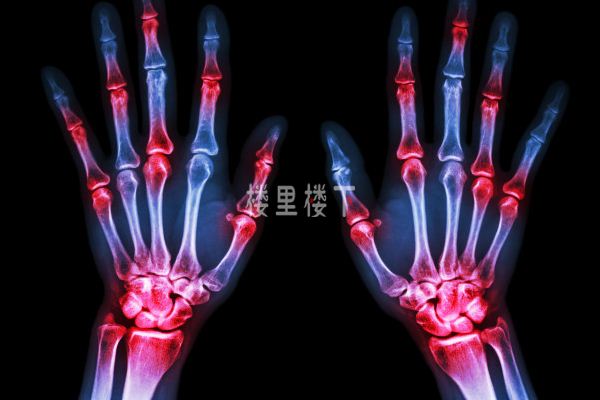

痛風是一種非常痛苦關節炎類疾病,不限年齡段且高發于男性,具體痛風的由來大家可以去網上搜索小曹這里就不去細說,簡單來說就是我們體內的嘌呤物質因為新陳代謝絮亂引發尿酸合成的增加或排出減少,最終造成高尿酸血癥且以鈉鹽的形式沉積在關節軟骨等部位引發痛風,通過堅持讓血尿酸降低并維持在合理水平,比如有痛風石的低于300μmol/L,沒有痛風石的低于360μmol/L以下,這樣就可以讓痛風較少發作甚至達到康復目的。